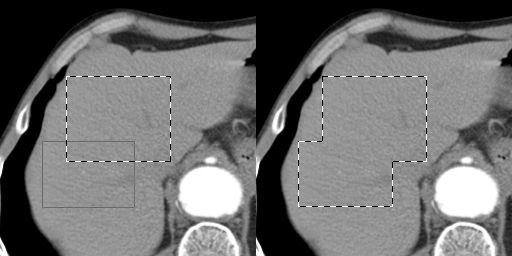

In the examples is used the selection rectangle tool.

Selection Addition

Before you select the second area hold down the <Shift> key of the keyboard, and then use your mouse for the second selection.

Selection Subtraction

Before you select the second area hold down the <Ctrl> key of the keyboard, and then use your mouse for the second selection.

Selection Intersection (common area)

Before you select the second area hold down the <Shift> and <Ctrl> keys of the keyboard, and then use your mouse for the second selection.